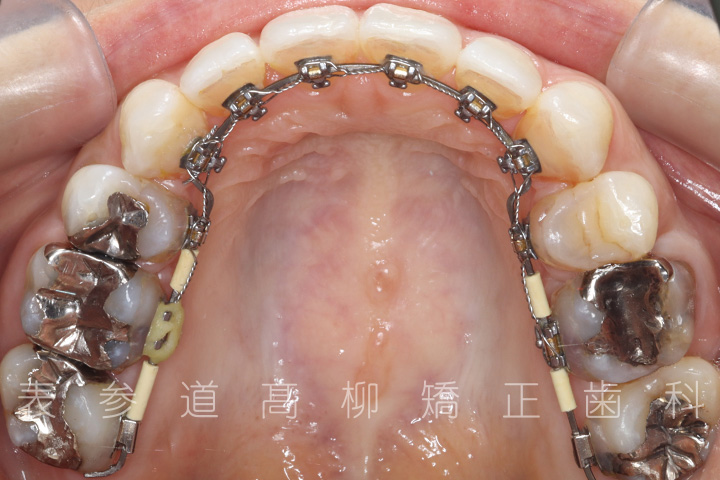

治療経過

• 治療開始

• 3ヶ月後

• 10ヶ月後

• 20ヶ月後

• 22ヶ月後

• 治療終了

・リンガルブラケット装置

・歯科矯正用アンカースクリュー(i-station)

・マウスピース型矯正装置